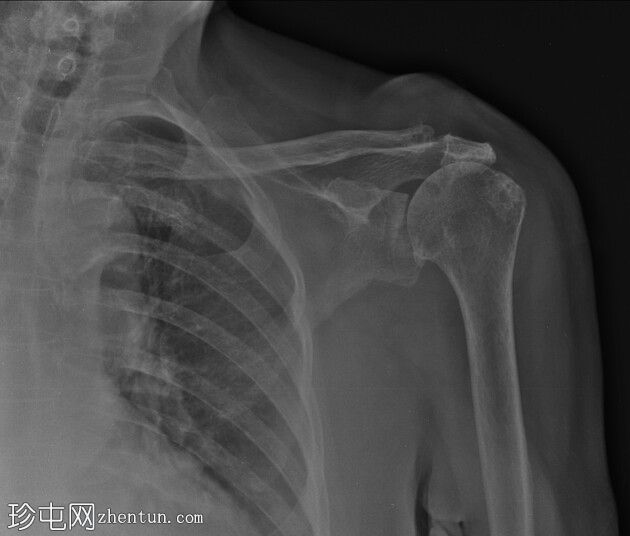

正位片 -

放大

站立位肩关节X线片最显著的发现是肱骨头近端移位,导致肩峰间隙变窄。其他发现包括:肱骨头大结节软骨下硬化和囊肿、肱骨头关节面软骨下囊肿、肩胛骨肩峰下表面软骨下硬化、肩胛盂上间隙变窄,以及锁骨外端颅侧小骨形成。左侧肩锁关节区域软组织肿胀,临床上可见肿块。未见骨折/脱位/骨损伤。